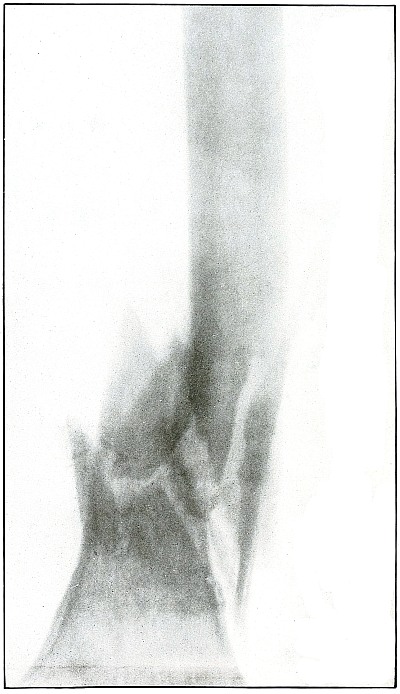

Plate 52.

[Pg 115]

Rifle—Plate 52.

LOWER EXTREMITY.

Gunshot Fracture of the Upper Shaft of the Femur.

The course of the bullet was anteroposterior and pierced the axis

of the shaft of the femur with three radiating lines of fracture,

resulting from the perforating action of the bullet striking the bone

at long range and with greatly reduced energy.

This plate shows the lateral separation of large fragments,

which is typical of gunshot wounds of long range.

Such wounds are usually not infected.

Emergency treatment is antiseptic dressing and coaptation with

extension and temporary splint, so that it may support the bone for

transportation and may be easily removable at place of continued

treatment.

In these cases with lateral separation of fragments, it is imperative

to supplement extension with pressure in a line perpendicular to the

long axis of the femur.

[Pg 116]